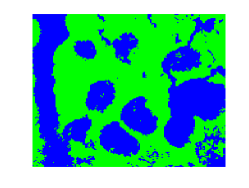

Hyper-spectral images are also used in medical applications such as detection of tissue anomalies. In this case a hyper-spectral microscope is used to capture hyper-spectral images of tissue samples. These images are analyzed in order to detect benign and malignant tumors [144, 145, 56]. Figure 1.3 shows two wavelengths of a hyper-spectral microscope-generated image of a human colon tissue. A more comprehensive introduction on hyper-spectral imagery, can be found in Chapter 5.

![]() |